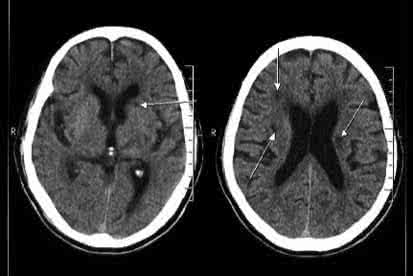

6、对突发头痛、头昏、眩晕、记忆力力减退、反应迟钝、遗忘、视物不清、面部发麻等症状,应提高警惕,尽早到医院做头颅CT,以便早发现早治疗。